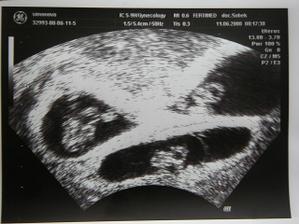

Holky se nám po skoro 4- letém snažení ,a po 1.IVF narodily 9.12.2008 ve 13:33,13:34,13:35, s mírama a váhama : Nela 2100g a 45cm, Gabriela 1860g a 43cm a Kristýna 2020g a 44cm.